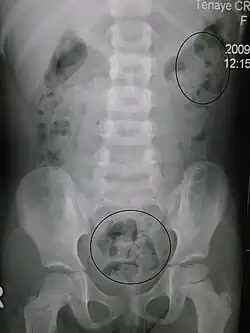

Constipation in a young child seen on X-ray. Circles represent areas of fecal matter (stool is white surrounded by black bowel gas).

Significant constipation in the plain X-ray of an 8-year-old

Abdominal X-rays are generally only performed if bowel obstruction is suspected, may reveal extensive impacted fecal matter in the colon, and may confirm or rule out other causes of similar symptoms.[26][17]